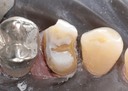

Joe Cha #18 pre-op